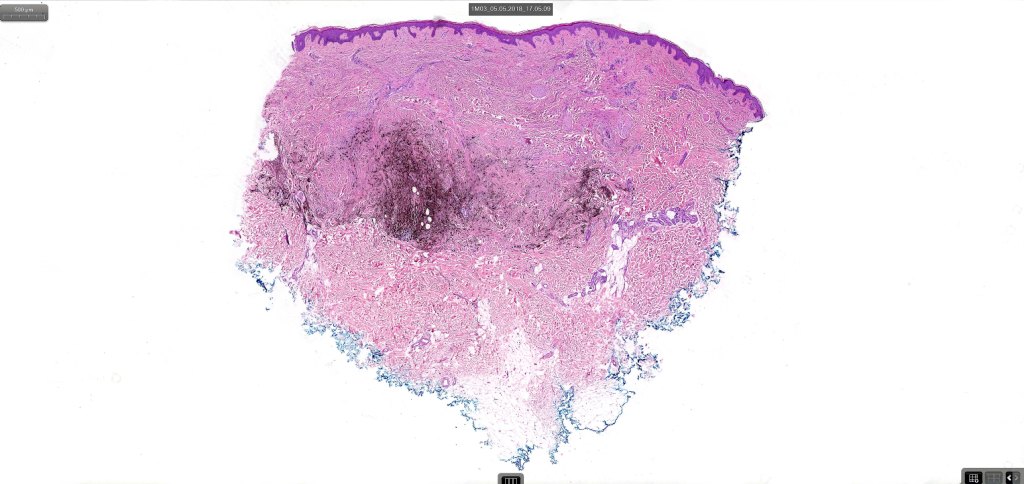

Cellular blue nevus

This uncommon most often devlops on the buttocks, sacrococcygeal region & distal extremities although it may be seen at just about any site. It shows a predilection for females and is diagnosed most often in the 2nd-4th decade. It presents as a blue-black/ or black nodule measuring 1-2 cm in dianeter. Similar to common blue nevus, the cellular variant can be encountered in a wide range of non-cutaneous locations.

•Most characteristic is the dumbbell silhouette although a plague morphology may also be encountered

•Combined nevus variant

•Admixture of spindle cells, pigmented bipolar or dendritic cells & melanophages

•Cytoplasm is pale and nuclei are small with inconspicuous nucleoli

•An alveolar pattern is characteristic particularly with clear cell nodules

•Mitoses are typically very sparse or absent

•No atypical mitoses

•No Necrosis or lymphovascular invasion

•Multinucleate giant cells sometimes present

•Stromal fibrosis, myxoid change, vascular hyalinization with cyst formation are often seen

•Some tumors are composed spindle cells in a fascicular or neuronevoid pattern

•Perineural involvement may be seen

•Balloon cell change

•Desmoplastic variant

•Hypopigmented variant